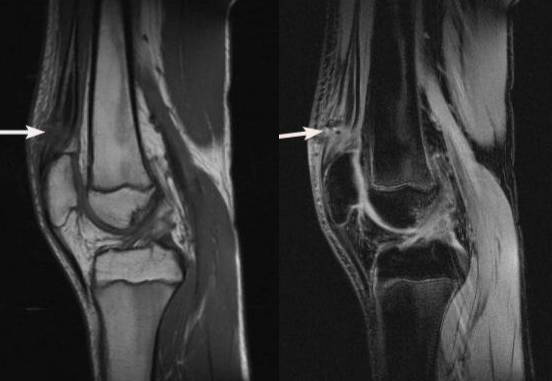

以内侧副韧带损伤(MCL)为例,可分为Ⅲ级

Ⅰ级:MCL 扭伤,可有水肿及出血;MRI 表现为损伤区T1WI 低信号,T2WI、STIR 呈高信号,在亚急性期出血时T1WI 可显示为高信号;而MCL的形态并不发生改变,与周围组织有明显的分界,冠状面上表现为平行于骨皮质的带状低信号影。

Ⅱ级:MCL 部分撕裂;Ⅱ级损伤,因韧带部分撕裂,水肿和出血使韧带和周围组织分界不清,其韧带可有移位,不再平行于骨皮质缘,部分纤维断裂处在T2WI 或STIR 上呈高信号。

Ⅲ级:MCL 完全断裂。Ⅲ级损伤,因韧带完全撕裂,使其连续性中断,并伴有韧带的增粗肿胀,整条韧带结构与肌肉信号混合,界限消失,不能辨认其结构走形,在T2WI 或STIR 上呈弥漫性高信号,有时韧带断端呈波浪状改变,关节囊内可见不等量的积液影像